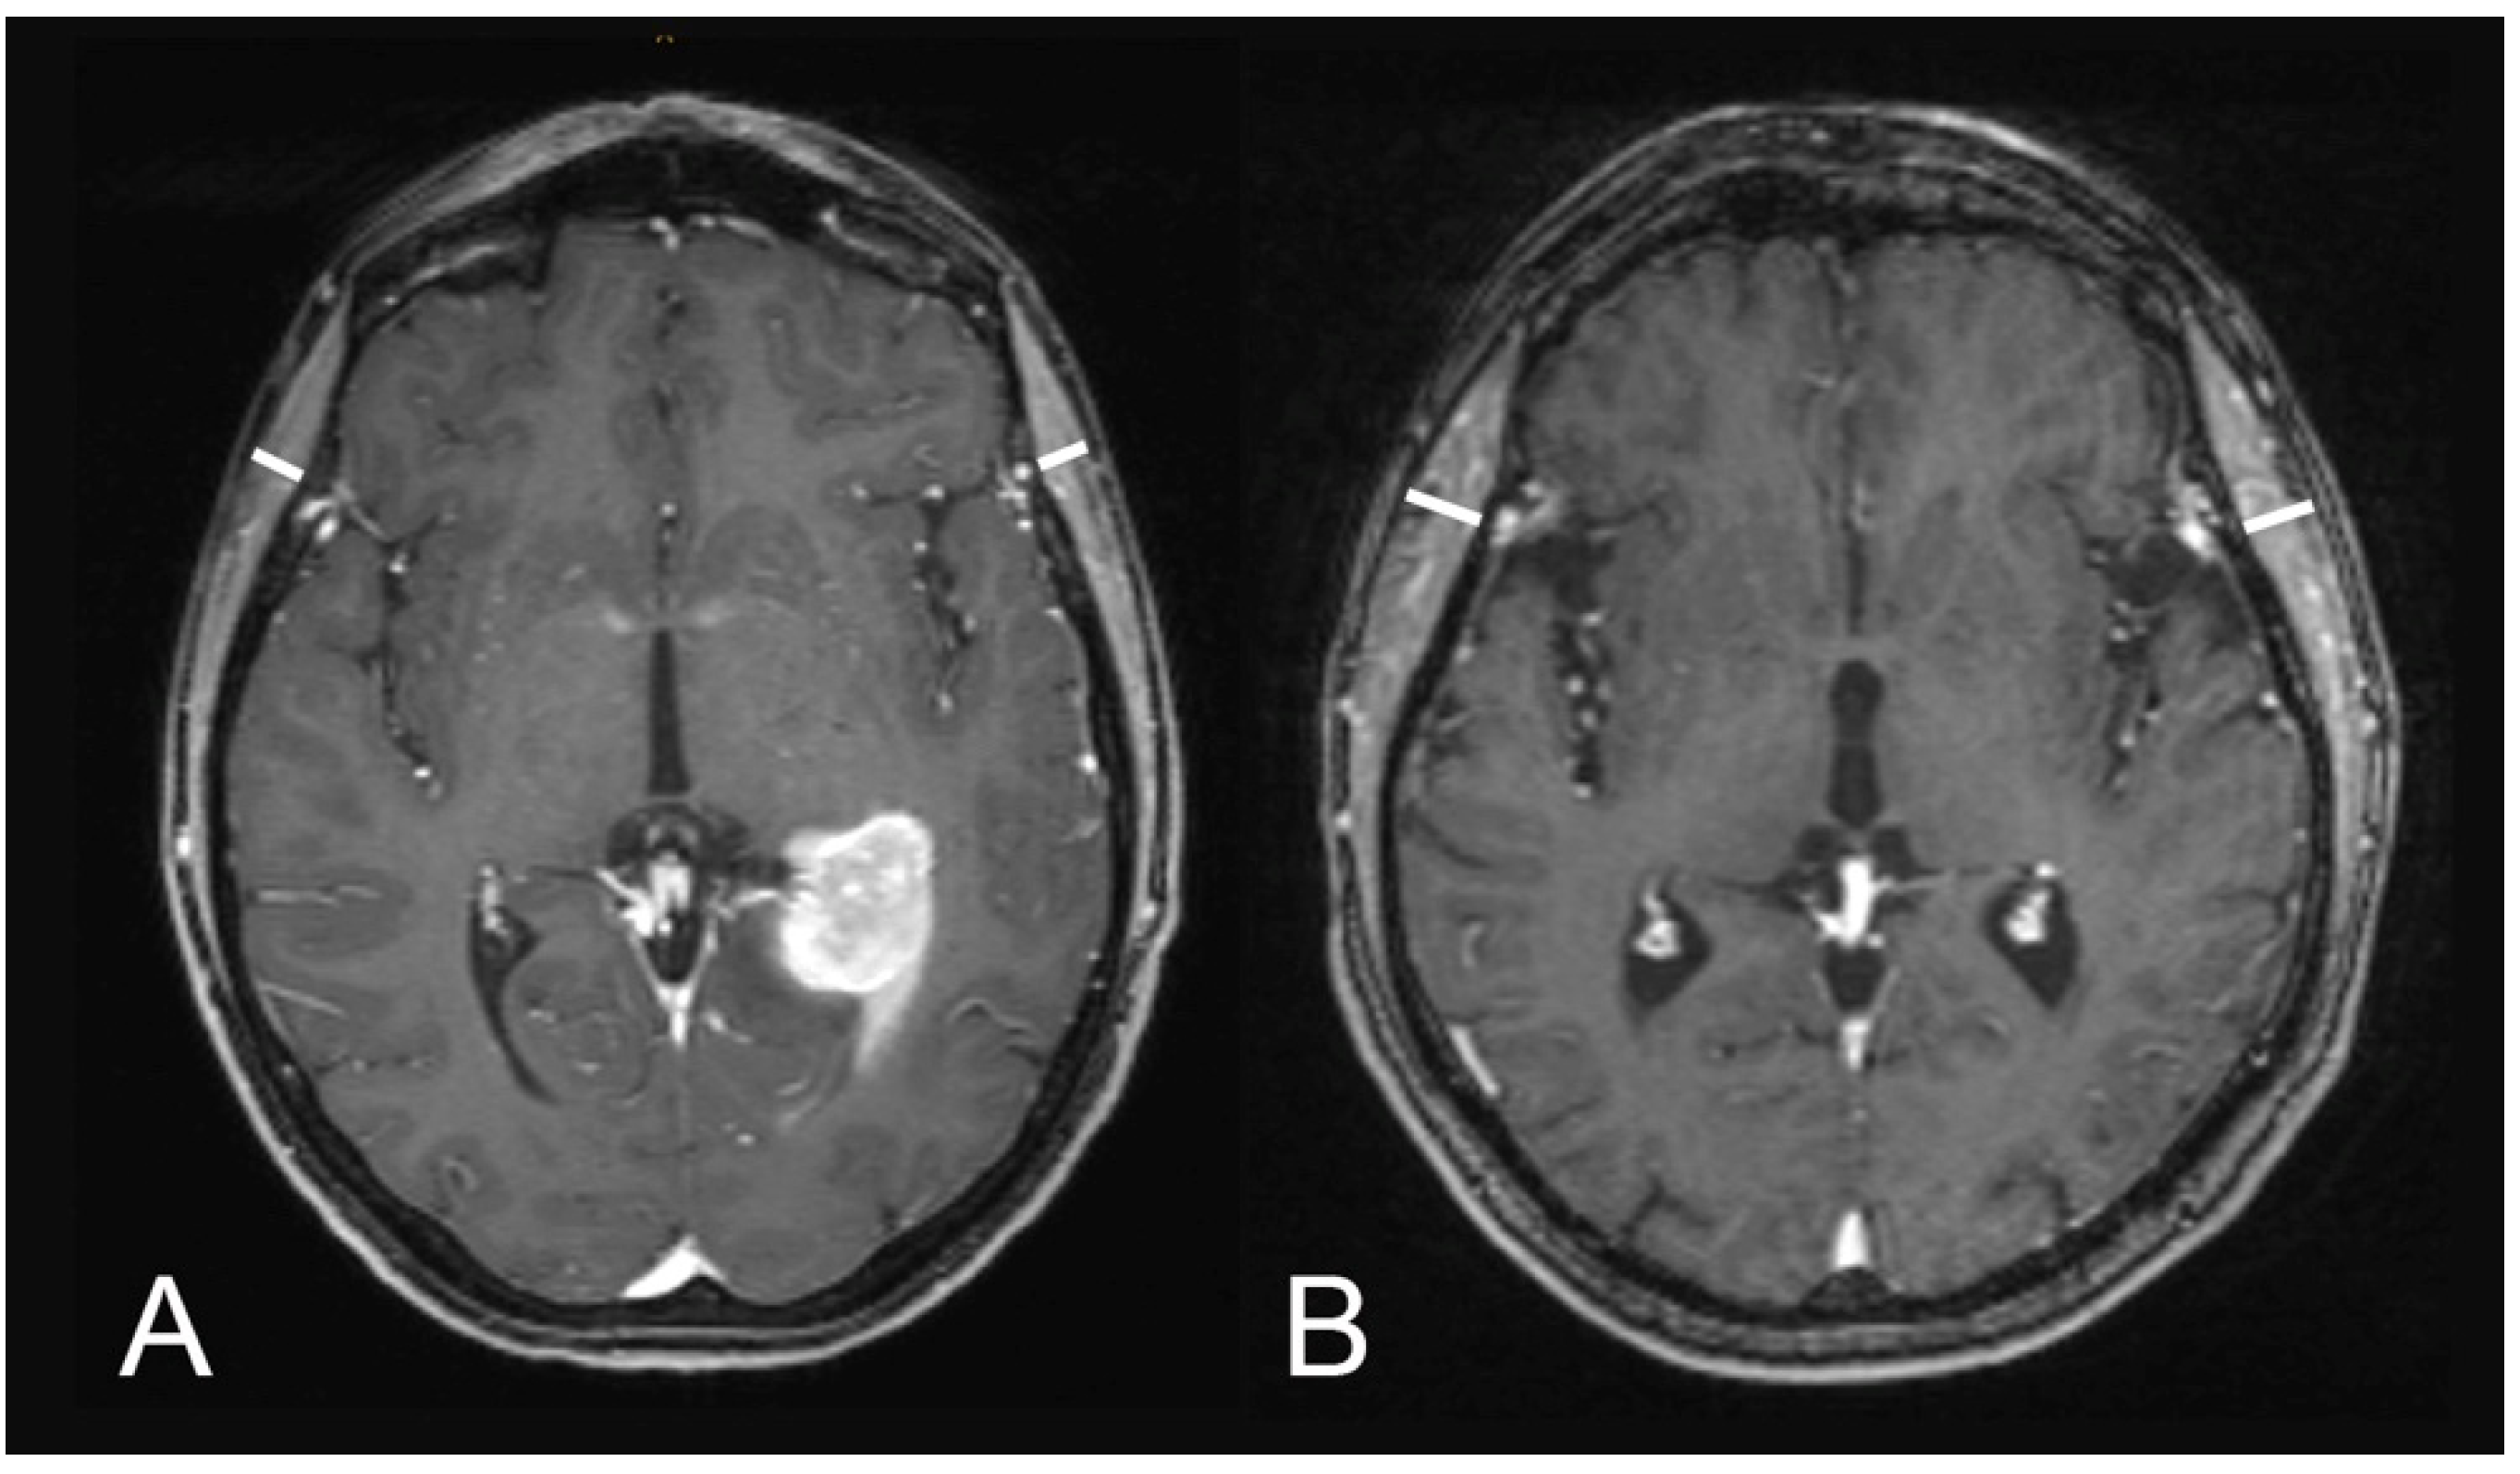

4.2. Assessment of Temporal Muscle Thickness